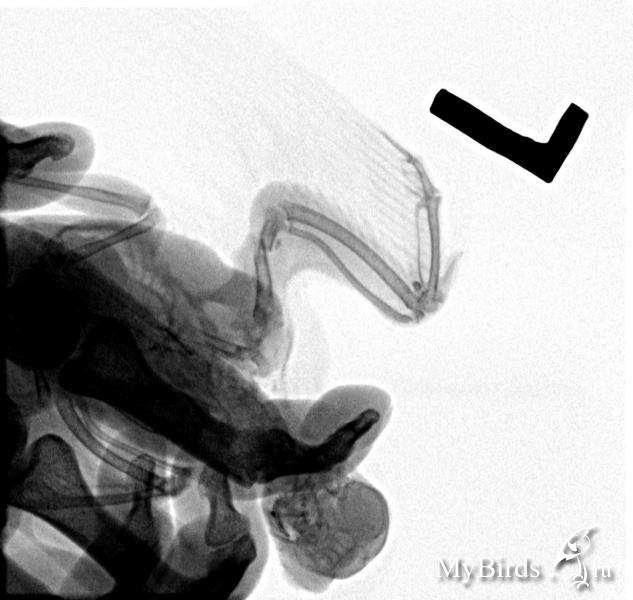

Рина Александровна Опубликовано 10 февраля, 2016 Автор #44 Опубликовано 10 февраля, 2016 Наконец-то мы дома. Тяжелый был день, особенно психологически.Рано утром я поехала в гнойно-ожоговое отделение в городскую больницу, покупать или выпрашивать колагеновую губку.Наслушалась про себя много хорошего. Сначала говорили , что такой губки у них нет. Потом вышла врач-санитар, и сказала, что губка есть, но "психам не выдаем". Я просила отрезать мне хоть кусочек, можно не стерильный. В общем, послали меня, практически прямым текстом. Наверное, надо было что-то придумать, про больного человека, а я правду сказала. Дура. Не дали губку. А в аптеках нет. Дальше поехали сдавать рентген. Снимок прилагаю. На снимке видно, как я нелепо сложила кость, а ещё видно маленький осколочек кости.

Рина Александровна Опубликовано 10 февраля, 2016 Автор #45 Опубликовано 10 февраля, 2016 Снимок сделали только один, хотя должны были два. Почему я так и не поняла, вроде как птицу нельзя так положить, как им было нужно. Но денег взяли меньше, если это утешительно. Со снимком отправились на факультет ветеринарной медицины. К заведующему, зовут Ковалев Паве Викторович.Кстати, у них там тоже не оказалось этих чудесных коллагеновых губок, которые я, следуя наставлениям Зоси везде-везде ищу. Посмотрел снимок, посмотрел Пикачу. Расспросил , что давали, как лечили. Расстроился, что сразу к нему не привезли. И сказал, что нужно ставить новую спицу. Потому что сильное смещение. И что рану придется заштопать. Я думала разревусь. Помню, как эту спицу в прошлый раз вставляли. Я уже настроилась , что он просто шину положит, и рану открытую оставит. чтобы я обрабатывала. С другой стороны, выставить правильно кость я, как становится видно по снимку, самостоятельно не смогла. Возможно, вы меня осудите, но я всё-таки решилась доверится врачу.Держала Пикачу. Бедный мой маленький герой, он даже не укусил меня ни разу. Эта операция отличалась от предыдущей. Во-первых врач очень тщательно почистил рану, достал этот маленький осколок, а кроме того, Пике предварительно сделали местное обезболивание. Всего этого не было в прошлый раз. Правда вокруг нас стояло человек пять студентов-девушек, но они не мешали и даже помогали. Рану постоянно, раза четыре то есть, проливали какой-то одной жидкостью, потом другой. Дальше спица. На этот раз чуть толще. Её ввели до самого конца, потом врач проверял крыло в разных положениях, в конце-концов торчащий кончик спицы отпилили крошечной циркулярной пилой, такой махонькой, не больше советских 10 копеек. Прямо под основание. А прошлая спица торчала где-то на 0,7. Вот. А я Пикачуню всё держу, держу и всё боюсь пальцы разжать или, наоборот сжать слишком сильно. И стараюсь улыбаться и ещё что-то подбадривающее врачу говорить и присутствующим, мелю какую-то чушь, а глаза не могу от раны отвести. Друзья, не приведи Господь, пусть вас всех минет чаша сия. Простите за лирику. Дальше рану зашили такой синей специальной ниткой и кривой иглой. В некоторых местах ткань крыла отходила кусочками, её приходилось прямо по ходу счищать. Я что заметила, что он ниткой и само место перелома такой петелькой дополнительно обкрутил, саму кость.Я ещё спрашиваю, а швы как потом снимать? Сказал, что они сами рассосутся, что нитка специальная, но это не кенгут, а как-то по-другому называется. Вот. Потом рану опять чем-то пролили и намазали "Инобиолем". Это мазь для гангренозных и трофических язв, как мне объяснили. Дальше доктор бинтом всё в несколько слоем промотал и сказал два раза в день щедро поливать хлоргексидином + диоксидином, допаить ципрофлоксацин, и в субботу на осмотр. Сказал, что если всё будет хорошо , всё должно зажить за 15 дней. Я так на это надеюсь. Может я и сама бы всё сделала , только вот губок нигде было не достать, а ещё снимок продемонстрировал мне мою полную криворукость. А я ещё ехала на рентген и думала, что будет на снимке только трещинку видно между обломкми кости, и что может и незачем мне этот снимок. Но очень рада, что сделали, увидели осколок, убрали. Это, по-моему, важно было. Фух. Спасибо огромное Зосе!!! За её терпение, помощь, внимание. Может я не была бы сегодня такой решительной, может сдали бы нервы, а так - держалась. Купили пиковит, глицерофосфат, таблетки с биотином для Пикачу. А себе - настоку пустырника. Пойду попью.

Для публикации сообщений создайте учётную запись или авторизуйтесь